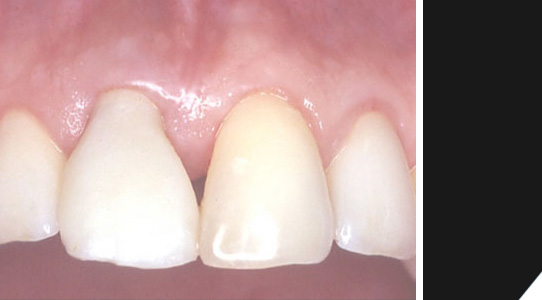

Zum Schluß erhält man ein optimales Ergebnis. Tragekomfort und Ästhetik lassen keine Wünsche offen. Der Zahnersatz ist praktisch nicht von natürlichen Zähnen zu unterscheiden.